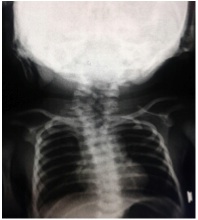

Riportiamo il caso di Mia nata a termine con TC da gravidanza gemellare. Per il riscontro di una formazione peduncolata a livello della guancia sinistra (Figura 2), tag preauricolari e auricolari bilateralmente e asimmetria dei rami mandibolari, venivano eseguite visita oculistica (nella norma), visita chirurgica plastica e Rx di torace e rachide cervicale (Figura 3), che ha evidenziato la presenza di multiple emivertebre nei tratti cervicale e dorsale, associate a difetto numerario delle coste di sinistra. Lo screening audiometrico (TEOAE+AABR) � risultato refer/refer.

Figura 3. Rx di torace e rachide cervicale che ha evidenziato la presenza di multiple emivertebre nei tratti cervicale e dorsale, associate a difetto numerario delle coste di sinistra.